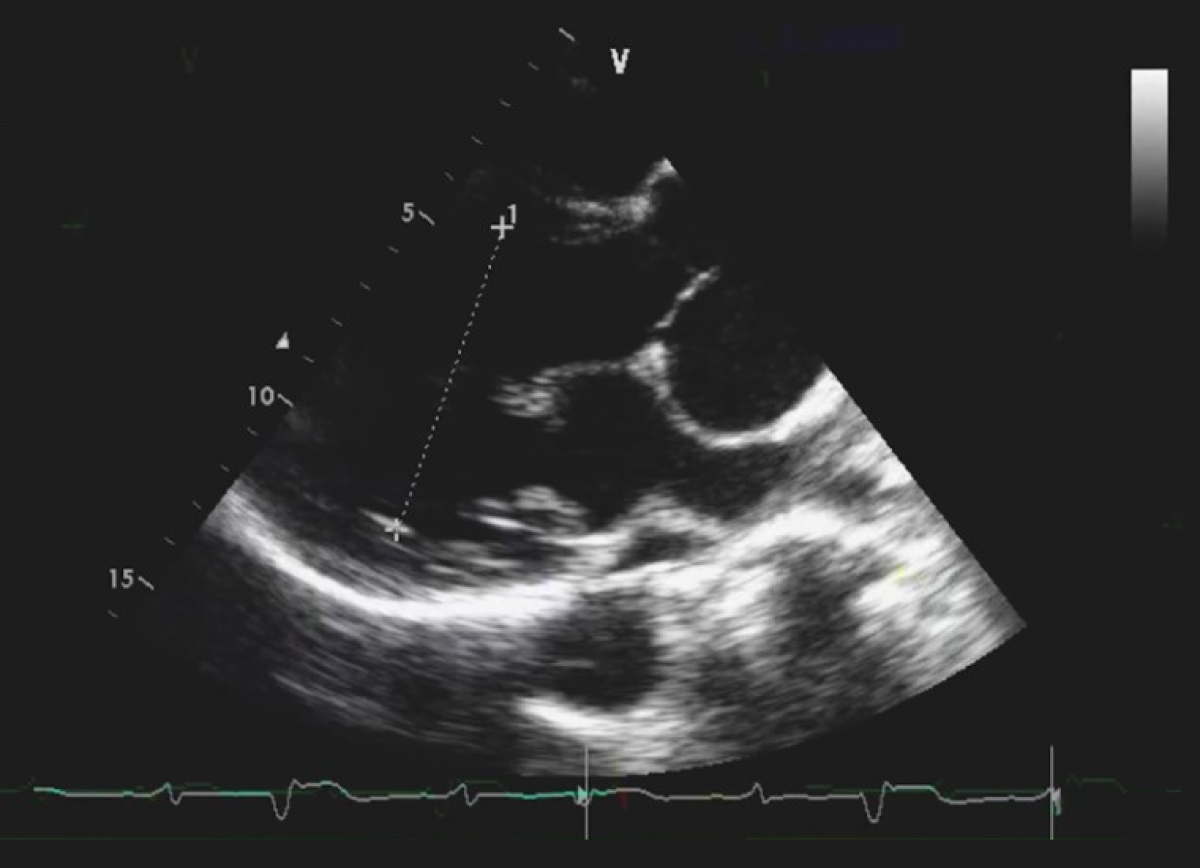

Troje pacjentów po korekcji wad wrodzonych, z objawami infekcyjnego zapalenia wsierdzia

Infekcyjne zapalenie wsierdzia u pacjenta po korekcji tetralogii Fallota

Infekcyjne zapalenie wsierdzia w obrębie biologicznej zastawki pnia płucnego wszczepionej przezcewnikowo

Echokardiografia przezklatkowa

Echokardiografia trójwymiarowa.

Diagnostyka echokardiograficzna infekcyjnego zapalenia wsierdzia

Ocena pacjentów po korekcji wady wrodzonej